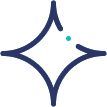

Acute Kidney Injury

Acute Kidney Injury (AKI), also known as acute renal failure, is a sudden decline in kidney function that

Chronic Kidney Disease

Chronic Kidney Disease (CKD) is a long-term condition in which the kidneys gradually lose their ability

Kidney Transplantation

Kidney transplantation is the most effective long-term treatment for patients with end-stage kidney

Kidney Biopsy

A kidney biopsy is a diagnostic procedure in which a small sample of kidney tissue is taken and examined

Kidney Stone Disease

Kidney Stone Disease occurs when hard mineral and salt deposits form inside the kidneys due to

Glomerular Diseases

Glomerular diseases are a group of conditions that damage the glomeruli, the tiny filtering units

Diabetic Kidney Disease

Diabetic Kidney Disease, also known as diabetic nephropathy, is a common and serious complication

Hypertensive Kidney Disease

Hypertensive Kidney Disease is a condition in which long-standing high blood pressure gradually